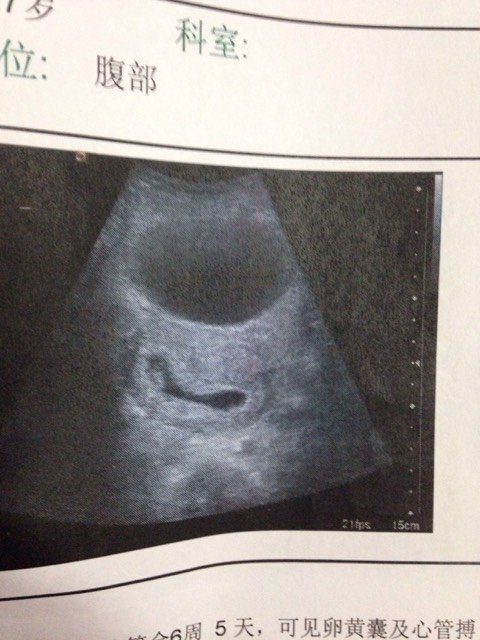

你们帮我看看为什么我比超那个单子上那个是孕囊吗?怎么那嘛长?像个茄子? 你们帮我看看为什么我比超那个单子上那个是孕囊吗?怎么那嘛长?像个茄子? 点击展开 123#(^V^) 2015-02-07 21:50 为您推荐: 其他回答 我感觉有点 踮脚尖望幸福 2015-02-08 11:54 是孕囊!! Candy_GTxL 2015-02-08 09:24 可能是男孩 大票嫲嫲 2015-02-07 23:24 这么长有可能会分裂成双胎,,还有要不然就是男孩的几率大些,恭喜恭喜宝妈 予薇 2015-02-07 22:49 男宝宝…… ~~_kltl 2015-02-07 22:35 加载更多 相关问题 怀孕两个月,帮我看看孕囊是茄子一样的,能确定是男孩吗? 怎么看B超单子上是茄子型还是园型 你好麻烦帮我看看这长四维彩超单子正常吗